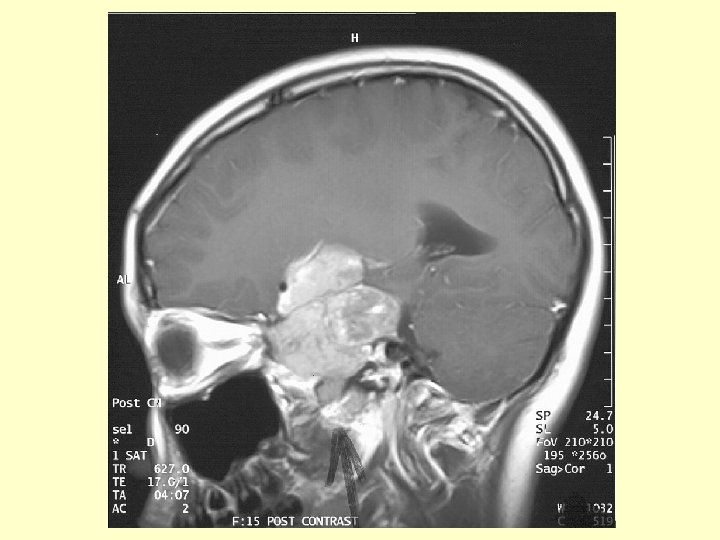

Investigation (3) • CT scan brain: A large hyperdense mass at the left parasellar region. It measured 4. 6 x 4. 4 cm. No calcification or cystic component found. It was extra-axial in location & extended into the pituitary fossa, middle & posterior cranial fossae. The left carotid artery was encased. The optic chiasm was compressed. There was mild hydrocephalus noted due to compression at level of Foramen of Monro.

Investigation (4) • MRI brain: A contrast enhanced solid tumor , measuring 4. 6 x 4. 8 x 6. 3 cm , was occupying whole sella with superior & inferior extension. Superiorly it extended to suprasellar cistern compressing left hypothalamus with the left cerebral peduncle being compressed & elevated. The frontal horn of left lateral ventricle was compressed from below. The left carotid artery was encased by tumor. The optic chiasm could not be identified but was likely to be compressed & encased.

Investigation (5) • MRI brain ( cont’d) Laterally the mass was compressing left temporal lobe & was occupying cavernous sinuses & Meckel’s cave. The mass also occupied right cavernous sinus & encasing right carotid artery. Inferiorly, the mass eroded through sellar floor & occupied sphenoid sinus with floor of sphenoid sinus preserved. Posteriorly the mass extended into left cerebellopontine angle cistern and caused compression of left of pons. Fourth ventricle not distorted.